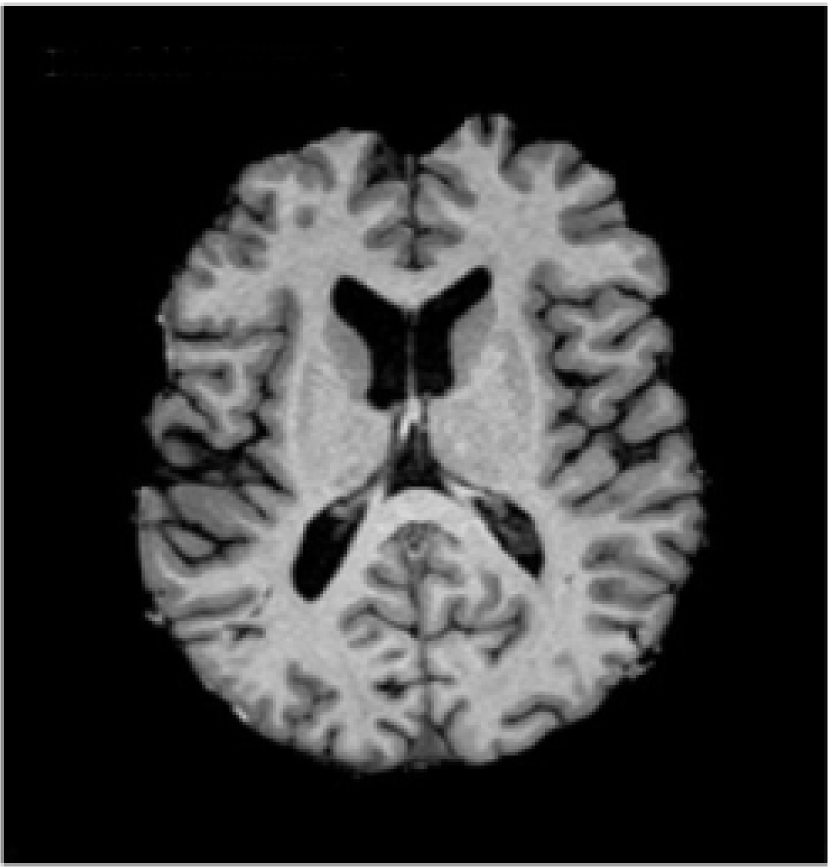

Acquired brain MRI volumes incorporate non-brain tissue parts of the head, such as eyes, fat, spinal cord or skull. The process of extracting the brain tissue from non-brain one is referred in the literature as skull stripping. An example of an original volume and its corresponding skull stripped output is presented in Fig. 4(a) and  4(b), respectively. This step has direct consequences on the performance of automated methods, as the inclusion of skull or eyes as brain tissue may lead to unexpected results in classification [102, 103], while unintended removal of the cortical surface may result in underestimation of the cortical thickness [104]. Among the different methods proposed in the literature for skull-stripping [105, 102, 106], methods such as BET [107, 108], BSE [109], ROBEX [110] and BEaST [111] are commonly used. In the literature, the methods used in clinical trail datasets employed BET [21, 25, 112] and ROBEX [23]. Zhang et al[26] applied a paediatric brain skull stripping algorithm known as LABEL [113]. The public dataset images from the Brain Tumor Image Segmentation Challenge (BRATS) 2013222http://martinos.org/qtim/miccai2013/, 2014333https://sites.google.com/site/miccaibrats2014/ and 2015444https://www.smir.ch/BRATS/Start2015 are preprocessed in this regard beforehand.

Refer to caption

(a) T1-w image

(b) Skull stripped

(c) Bias field

(d) Preprocessed T1-w

Figure 4: An example of two preprocessing methods: skull stripping and bias field correction [114]. In the figure, a T1-w slice is displayed in (a), brain tissue after removing non-brain areas in (b), estimated bias field in (c), and preprocessed brain tissue in (d).

Inherent characteristics of the MRI acquisition process such as differences in the magnetic field, bandwidth filtering of the data or eddy currents driven by field gradients usually result in image artefacts that may also have a negative impact on the performance of the methods [115]. There is the need to remove spurious intensity variations caused by inhomogeneity of the magnetic fields and coils. In these cases, intensity correction of the MRI images is performed either before tissue segmentation, or as an integrated part of the tissue segmentation pipeline. A common technique to address this problem is to use bias-field correction [116]. The estimated bias field and the corrected version of Fig. 4(b) are depicted in Fig. 4(c) and 4(d), respectively. Among the available strategies [117, 118], the non-parametric non-uniform intensity normalisation (N3) [119] and N4ITK [120] methods are currently the most widely used. Zhang et al[26] and Yoo et al[112] employed N3 algorithms on their clinical dataset. Similarly, Pereira et al[22] used them in both BRATS 2013 and 2015 Challenges, Lyksborg et al[121] in BRATS 2014, and Zikic et al[122] in BRATS 2013.